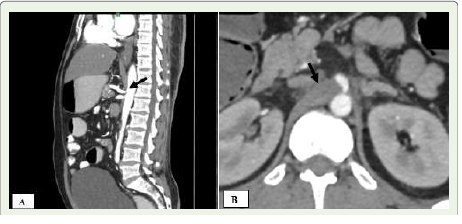

during CT imaging for unrelated issues [1,7,8] [Figure 2].CT imaging findings:

Multidetector CT (MDCT), due to its high spatial resolution,

enables clear visualization of the median arcuate ligament—thickness

beyond 4 mm is considered abnormal [8] [Figure 1B]. Since axial

images may not reveal the full extent of compression, sagittal

reconstructions are essential to assess both the ligament and celiac

artery origin. A distinctive hooked or “J-shaped” narrowing at the

origin of the celiac artery (Figure1A) serves as a key imaging sign

distinguishing MALS from atherosclerotic changes. The compression

is often persistent, even during inspiration. Additional findings may

include post-stenotic dilatation and development of collateral vessels

such as the pancreaticoduodenal arcade from the superior mesenteric

artery [9].Management:

Figure 1A and B:A 49-year-old man presenting with abdominal pain after

meals. (A) Sagittal contrast-enhanced CT angiogram of the abdomen

reveals a prominent median arcuate ligament (black arrow), causing a

hooked deformity and narrowing at the proximal celiac artery with poststenotic

dilatation. (B) Axial contrast-enhanced CT angiogram demonstrates

the celiac artery origin being compressed by the thickened median arcuate

ligament (black arrow).